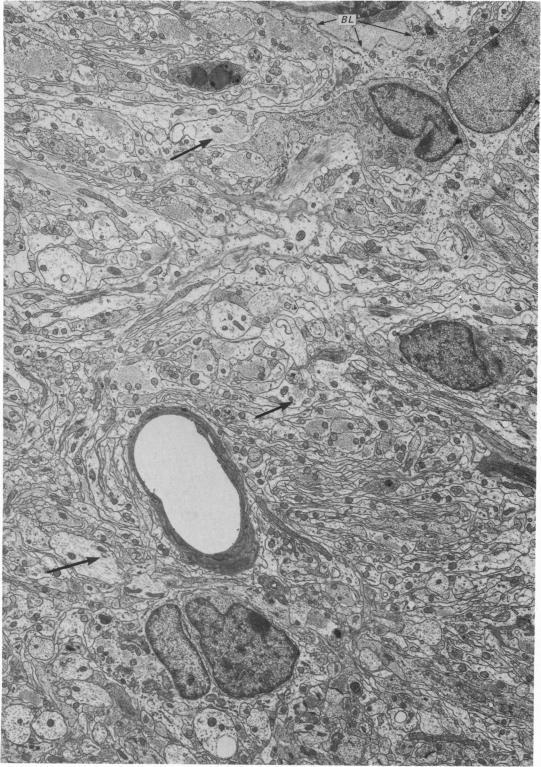

The re-innervation of the olfactory bulb has been studied in rats in which the primary afferent axons were transected either in the peripheral nervous system, on the intracranial side of the cribriform plate, or in the central nervous system, in the nerve fibre layer of the bulb. Both procedures resulted in denervation of glomeruli on the dorsal surface of the olfactory bulb. Re-innervation of these glomeruli was first seen approximately three weeks after operation and was largely completed by the sixth week, irrespective of the site of the lesion. The similarity of the timing of re-innervation following the two procedures indicates that the cut fibres did not regenerate from their sites of transection. It is much more probable that the re-innervation axons were those of neurons newly generated in the olfactory epithelium. This view is supported by the results of other investigations, in which retrograde degeneration and subsequent replacement of the neurons have been found to follow transection of the olfactory nerves. After transection of the olfactory nerves, the new axons entering the bulb grew through the site of the lesion, across the interface between peripheral and central nervous tissue, through the nerve fibre layer and into the glomeruli. Thus, they followed the same course as normally growing primary olfactory axons. After the afferent fibres had been cut within the olfactory bulb, the site of transection was transformed into a scar composed largely of astrocytes. No olfactory axons grew through the scar and none passed beneath it in the deeper layers of the bulb. However, by tracing the anterograde axonal transport of horseradish peroxidase, it has been shown that axons immediately rostral to the lesion terminated in the re-innervated glomeruli. These denervated glomeruli were, therefore, probably re-innervated by axons that grew through the intact central nervous tissue of the nerve fibre layer on either side of the lesion.